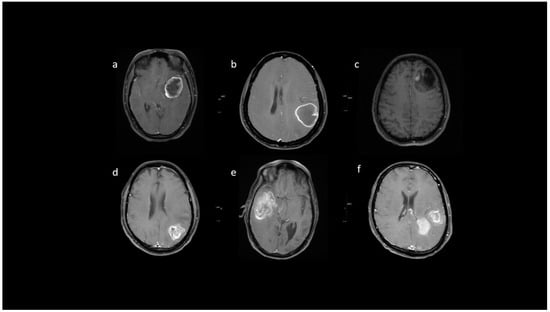

3.2. MRI Parameters of IDH-Wildtype vs. Mutant Phenotype Tumors

| Variable | Parameter | IDH-Mutated (n = 19) | IDH-Wildtype (n = 129) | p-Value |

|---|---|---|---|---|

| Enhancement I | Mild | 9 (47.4) | 5 (3.9) | <0.001 |

| Moderate | 6 (31.6) | 25 (19.4) | ||

| Severe | 4 (21.1) | 99 (76.7) | ||

| Enhancement III | Rim | 6 (31.6) | 104 (80.6) | <0.001 |

| Nodular | 0 | 2 (1.6) | ||

| Patchy | 11 (57.9) | 13 (10.1) | ||

| Solid | 2 (10.5) | 10 (7.8) | ||

| Necrosis | None | 3 (15.8) | 3 (2.3) | <0.001 |

| <25% | 11 (57.9) | 14 (10.9) | ||

| 25- 50% | 2 (10.5) | 35 (27.1) | ||

| >50% | 3 (15.8) | 77 (59.7) | ||

| Dural enhancement | AbsentPresent | 07 (70.0) | 31 (24.0)48 (52.7) | 0.013 |

| Edema | None | 3 (15.8) | 3 (2.3) | 0.025 |

| <tumor volume | 11 (57.9) | 68 (52.7) | ||

| Equal to tumor volume | 4 (21.1) | 35 (27.1) | ||

| >tumor volume | 1 (5.3) | 23 (17.8) | ||

| Cysts * | No | 11 (57.9) | 115 (89.1) | 0.001 |

| Yes | 6 (31.6) | 14 (10.9) | ||

| Subcortical involvement | Involved | 18 (94.7) | 94 (72.9) | 0.044 |

| Not involved | 1 (5.3) | 35 (27.1) | ||

| rCBV | Median (IQR) | 1.8 [1.4–2.0] | 2.6 [1.9–3.5] | 0.001 |